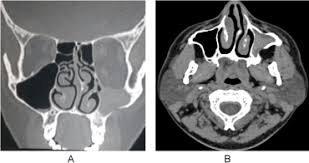

The visual sign of silent sinus syndrome is the asymmetry of the face and the asymmetry of face may lead to many other problems like diplopia. Recent findings Silent sinus syndrome lies on a spectrum of other forms of sinus-related orbitopathy. Radiographic features of disease include an opacified and hypoplastic sinus a lateralized uncinate process depression of the orbital.

The first case of maxillary sinus opacification and atelectasis was reported by Montgomery in 1964 It was not until 30 years later however that the term silent sinus syndrome was attributed to this phenomenon Patients typically present with unilateral painless enophthalmos and hypoglobus progressing over a period of several months. The silent sinus syndrome is characterized by painless enophthalmos associated with involution of the maxillary sinus after infundibular occlusion 12345678910. The hypoventilation over time results in resorption of.

Silent sinus syndrome is a rare condition that can pose a diagnostic challenge. One such disease process silent sinus syndrome is a progressive condition in which maxillary sinus pathology causes inferior displacement of the orbital floor resulting in enophthalmos and hypoglobus.

Silent sinus syndrome is rare and multiple findings are needed for the diagnosis. The hypoventilation over time results in resorption of. Diplopia is seen in about 28 to 65 of cases regarding silent sinus syndrome. Silent sinus syndrome is more common in patients in their 30s and 40s ranging from 19 to 82 years mean 39 without gender or laterality bias. These include enophthalmos or hypoglobus in the absence of clinically evident sinonasal inflammatory disease. The first case of maxillary sinus opacification and atelectasis was reported by Montgomery in 1964 It was not until 30 years later however that the term silent sinus syndrome was attributed to this phenomenon Patients typically present with unilateral painless enophthalmos and hypoglobus progressing over a period of several months. 5 The proposed mechanism for the development of silent sinus syndrome is a hypoventilated maxillary sinus from an obstructed ostiomeatal complex. The silent sinus syndrome is a spontaneous unilateral maxillary atelectasis with complete or partial opacification of the sinus. The silent sinus syndrome is a rare clinical entity of spontaneous enophthalmos and hypoglobus caused by an alteration of the normal orbital architecture and function from maxillary sinus collapse in the setting of chronic sinusitis.

When looking at all the pictures on google the symptoms its all matching. Ocular motility limitation also occur and sometimes reported along with hypo Globus. Silent sinus syndrome is more common in patients in their 30s and 40s ranging from 19 to 82 years mean 39 without gender or laterality bias. Silent sinus syndrome is usually diagnosed in patients in their 30s and 40s with a mean age of 39 and a range of 19 to 82 11. Radiographic features of disease include an opacified and hypoplastic sinus a lateralized uncinate process depression of the orbital. Uncommon presentations and descriptions of sinus involvement other than the maxillary sinus add to the variability of presentation. These include enophthalmos or hypoglobus in the absence of clinically evident sinonasal inflammatory disease.